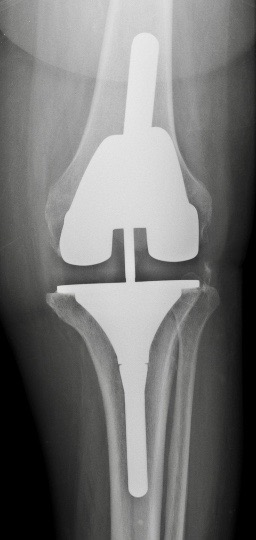

1. PTG

A. PTG à glissement +/- bouton patellaire

le plus couramment utilisé

pour les déformations petites et moyennes

remplace les ligaments croisés

Les ligaments latéraux doivent être en bon état pour assurer une bonne stabilité.